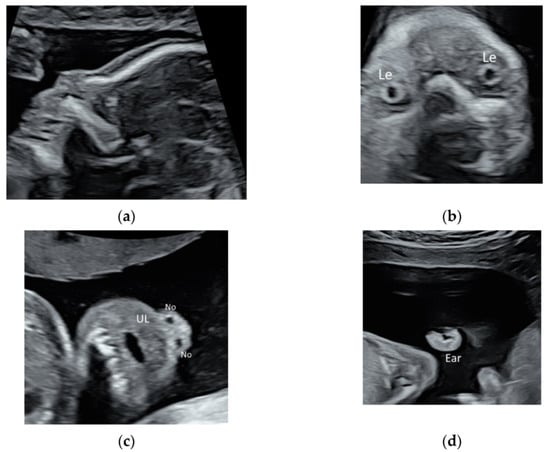

2.2. Face and Neck

- Mak, A.S.L.; Leung, K.Y. Prenatal ultrasonography of craniofacial abnormalities. Ultrasonography 2019, 38, 13–24. [Google Scholar] [CrossRef] [Green Version]